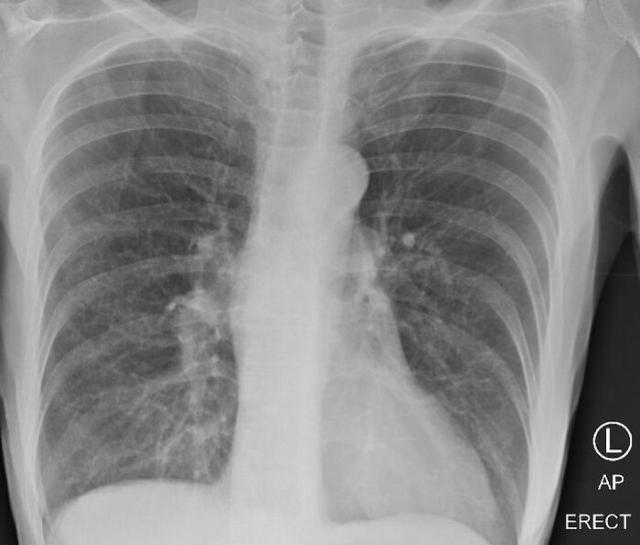

医生发布了三张肺部X光的照片,其中一名健康患者,一名吸烟者和一名COVID-19患者,以指出差异。

吸烟者肺部的X光照片,您会发现有些朦胧现象表明疤痕和充血。